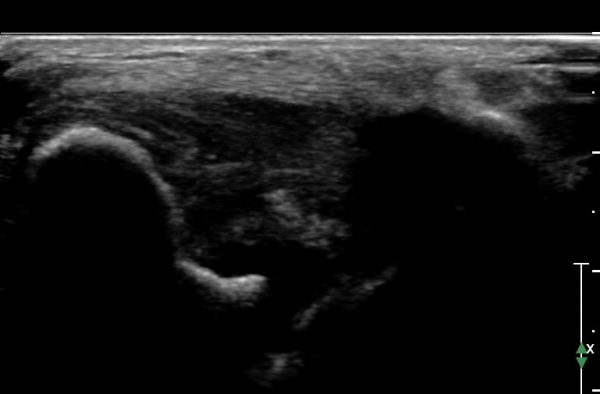

Àü°ÅºñÀδë ÇϺΠÁ¾´Ü¸é°Ë»ç¿¡¼­ Àü°ÅºñÀδëÀÇ Àú¿¡ÄÚ À§Ãø°ú Á·±Ùµ¿ÀÇ ¼ö¾×Àú·ù°¡

°üÂûµÈ´Ù(»çÁø 2, 3, 4).